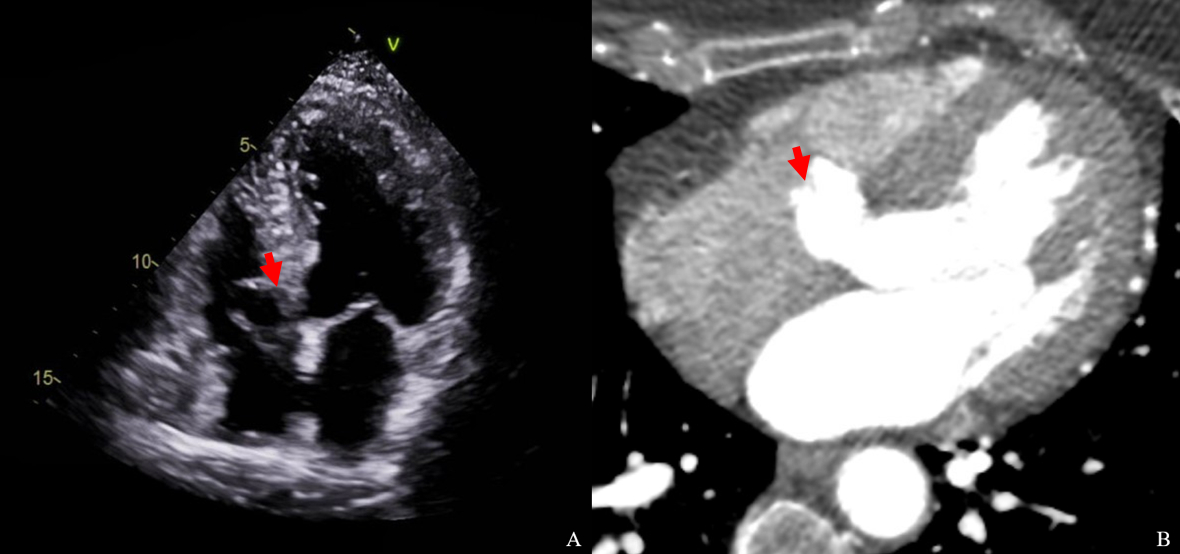

Results: From 51,732 subjects, 18 were identified with IVMS aneurysms, yielding a prevalence of 0.04%. Four patients with significant structural heart disease were excluded, resulting in a final sample size of 14. Of these, 9 (64%) were female with a mean age of 59.6, and 5 (36%) were male with a mean age of 55.4. The mean BMI was 27.9 kg/m2, with 4 classified as obese. All patients were nonsmokers; 2 had a family history of stroke. One patient had diabetes, 8 had hyperlipidemia, and 9 had hypertension. Only one patient had paroxysmal atrial fibrillation, with a CHA2DS2-VASc score of 0. Echocardiography revealed structurally normal hearts with a mean left ventricular ejection fraction of 61% and a mean left atrial volume index of 24.8 mL/m2. The mean neck diameter of the aneurysm was 8.7 mm, and the mean diameter was 11.9 mm. Two patients had inter-atrial septal aneurysms, and one had a patent foramen ovale.